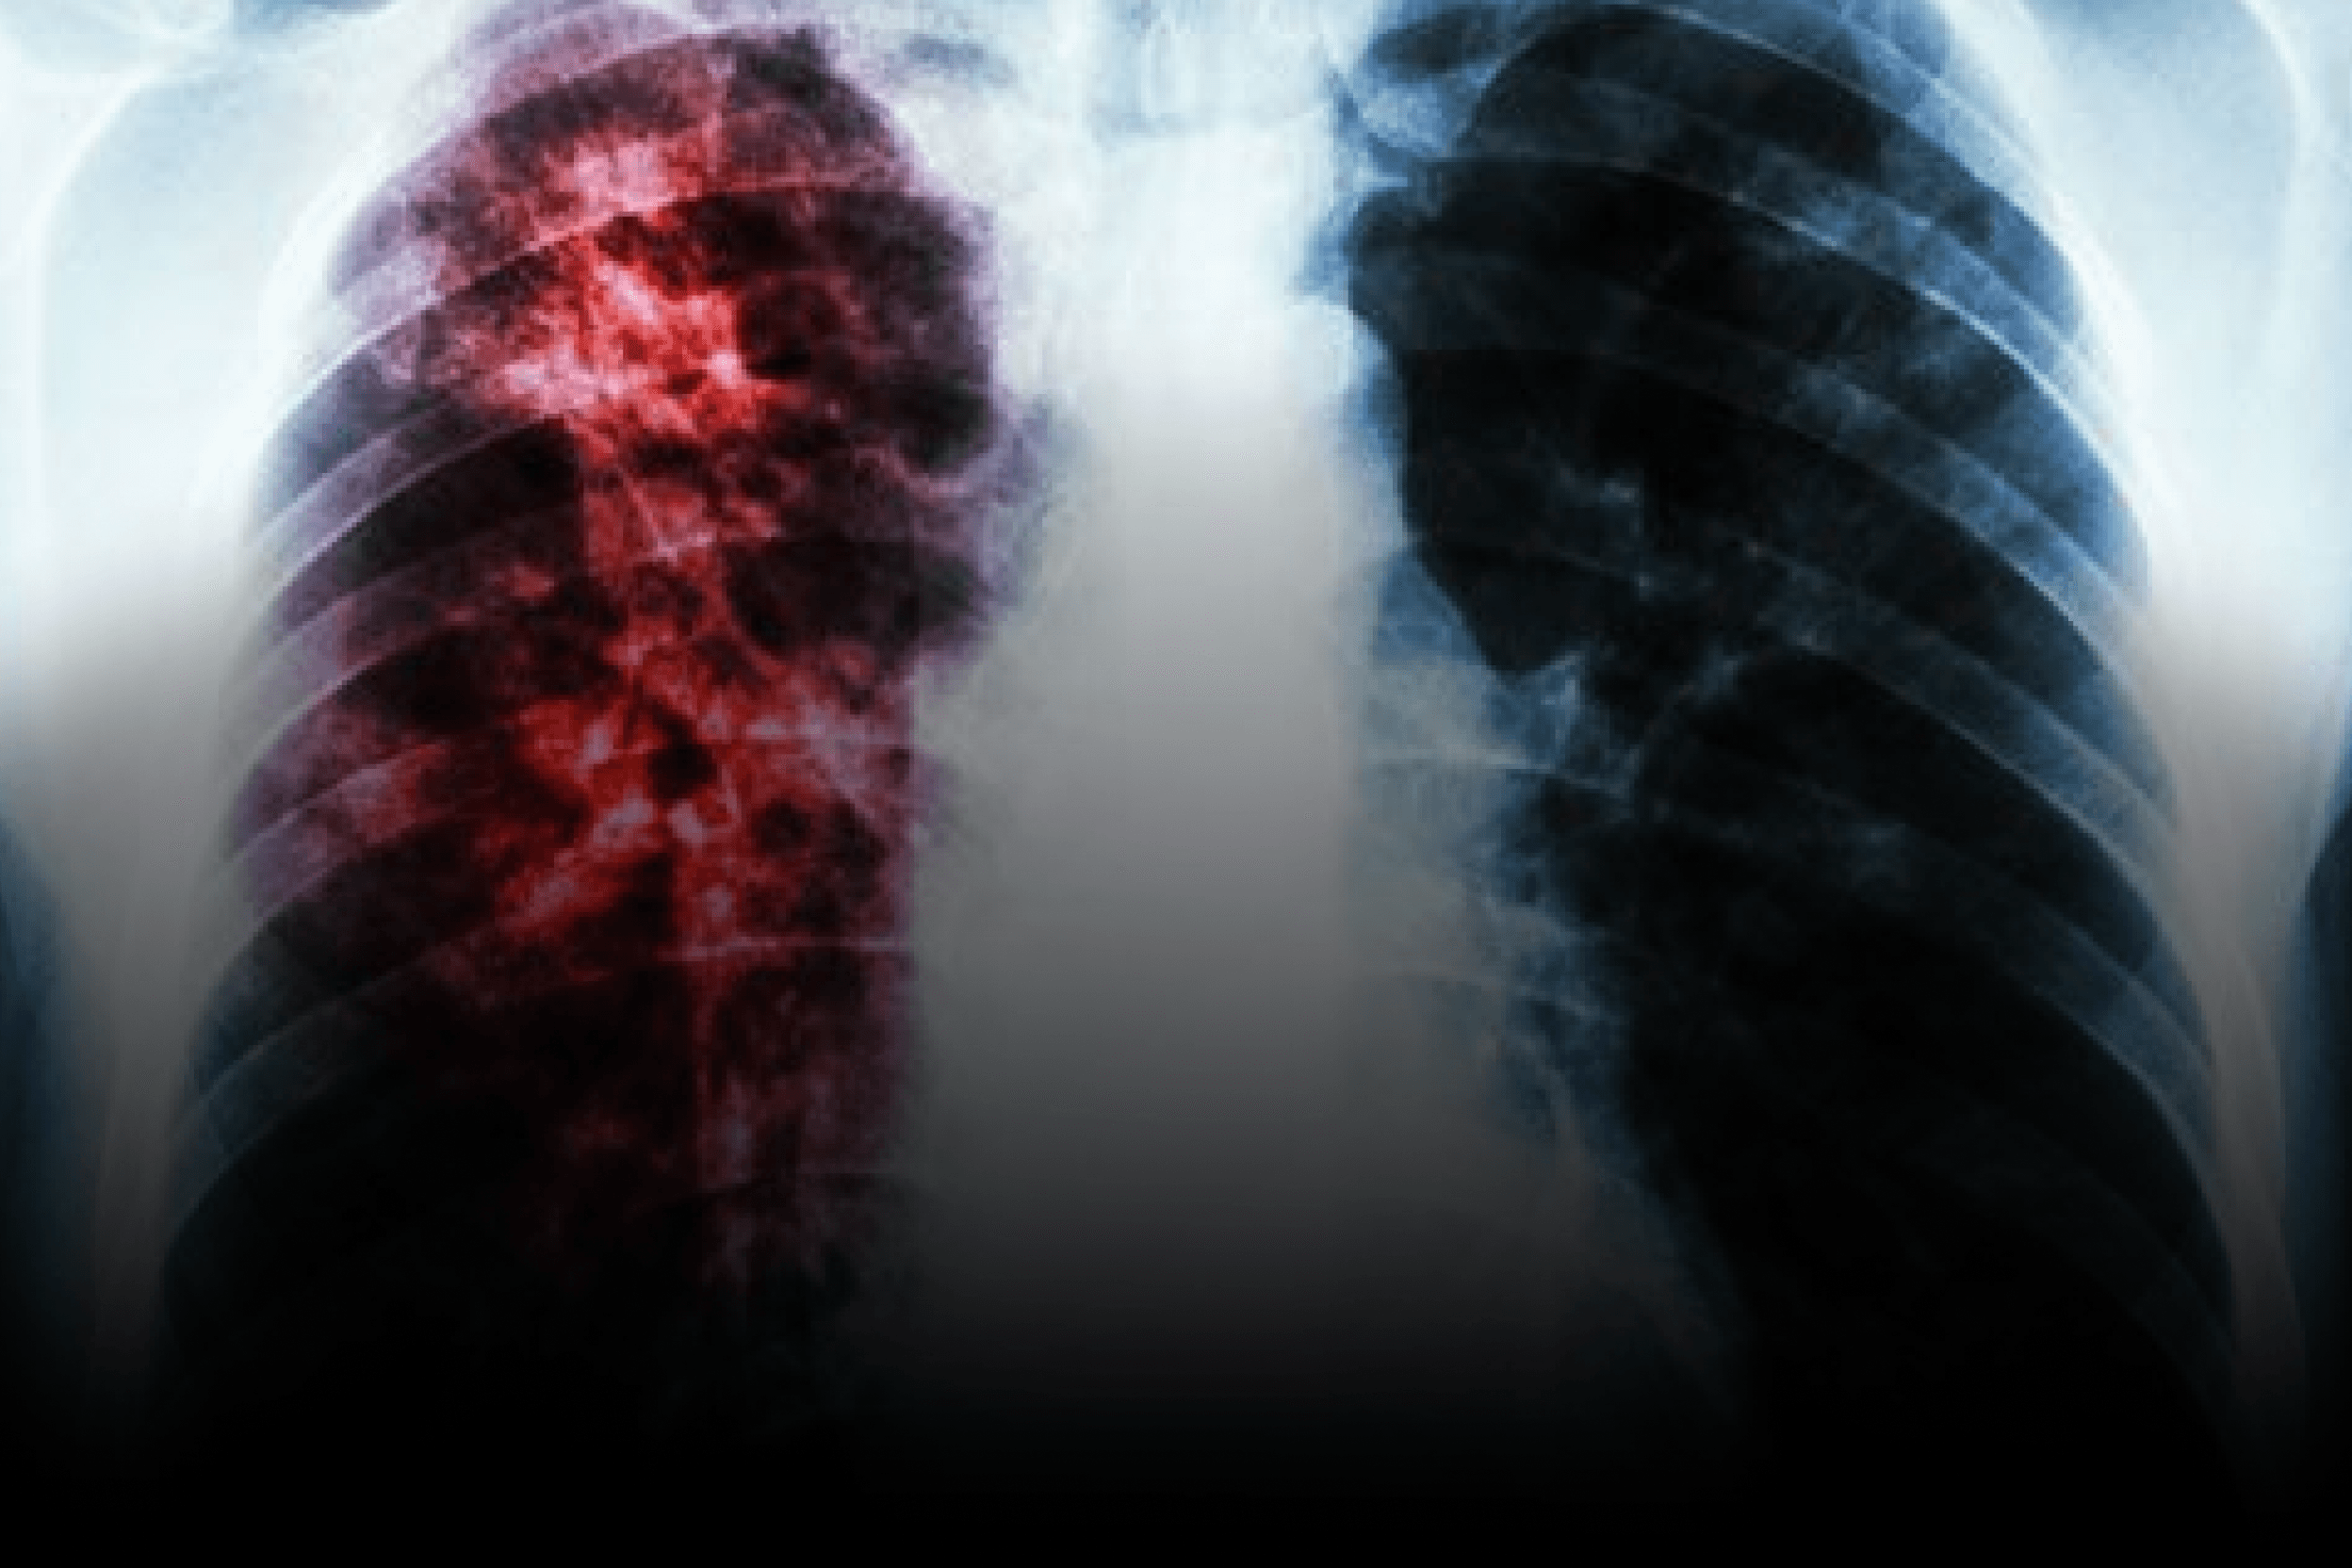

Avanço no tratamento da tuberculose resistente

Em meio ao aumento de cepas resistentes e aos desafios de adesão terapêutica, um novo antibiótico para tuberculose surge como promessa para mudar o padrão de cuidado. Dados preliminares de estudo fase 2, apoiado por entidades dos EUA, indicam maior eficácia em comparação a opções tradicionais, sem aumento de eventos de segurança. Para o Brasil, onde a tuberculose segue como importante causa de morbimortalidade e a resistência a fármacos preocupa serviços de referência, o avanço soma-se ao movimento global por esquemas totalmente orais e mais curtos — como os já discutidos no país (por exemplo, BPaL) — reforçando a relevância de antibióticos inovadores em estratégias atuais de controle.